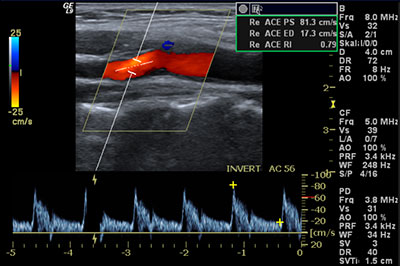

Die Duplexsonographie (kurz "Duplex"), auch farbkodierte Duplexsonographie oder Farbduplexsonographie genannt, ist eine mit Ultraschallwellen arbeitende Methode zur Untersuchung der Blutgefäße.

Der Zusatz "Duplex" besagt, dass zwei Informationen gleichzeitig geliefert werden können. Zum einen zeigt die Duplexsonographie ein Bild des Blutgefäßes (wahlweise in Farbe oder schwarz/weiß), zum anderen kann die Duplexsonographie gleichzeitig die Strömungsgeschwindigkeit des Blutes in dem untersuchten Gefäß messen.

Die Duplexsonographie dient der Untersuchung von Herz und Gefäßen und ermöglicht die Bestimmung des Butfusses, wobei die untersuchte Region als zweidimensionales farbiges Bild gleichzeitig mit der Flusskurve auf einem Monitor abgebildet wird.

Abbildung: Duplexsonographie einer Halsschlagader.